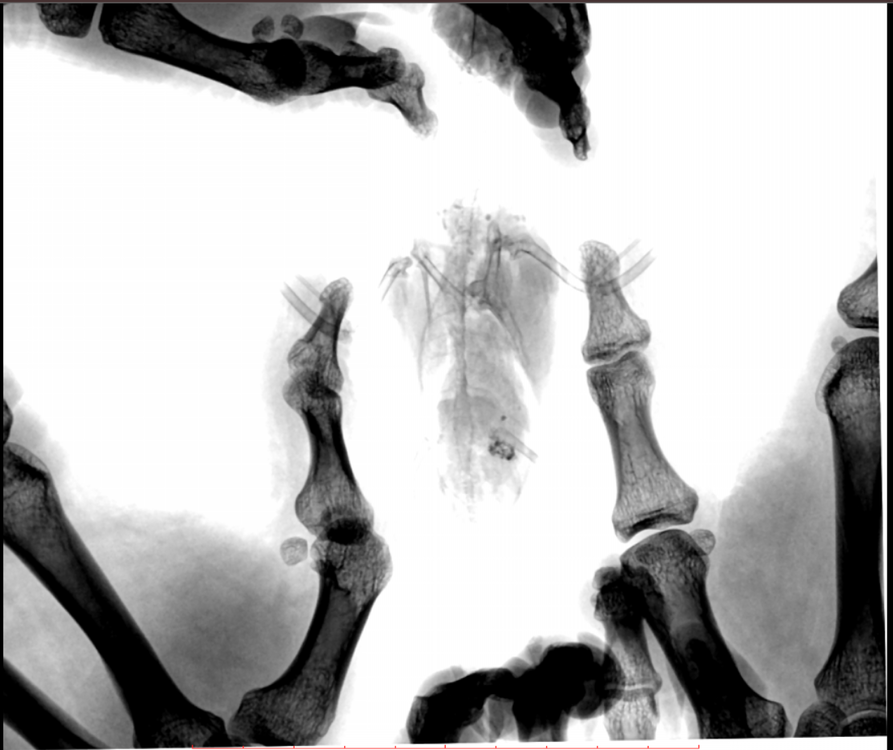

Во вторник отвозила птицу на рентген. Врач сказала, что очень сильно увеличена печень и другие органы. Также сдавлены воздухоносные мешки (из-за увеличенных внутренних органов). Отсюда - одышка. Также врач нашла перелом (старый?) ключицы. Попугая было очень сложно удерживать, поэтому снимки получились, возможно, недостаточно информативными - но какие уж получились((

@Zosia здравствуйте! Посмотрите, пожалуйста, снимки - видите ли вы на них отклонения, опухоли? Есть ли какие-то патологии? И одобряете ли вы назначенное лечение в нашей ситуации? Спасибо!

2.jpg

4.jpg

Печень видится мне увеличенной, но нужно чтобы @Zosia достоверно прочла снимки.

ответ: я увидела на снимках запущенную пневмонию, увеличенные семенники (и возможно опухоль на них), увидела в помете много палочек. Отсюда - назначение.

6.Тень семенников действительноу величена. Но снимок вами показан дурного качества. И бОльшего я сказать не могу.